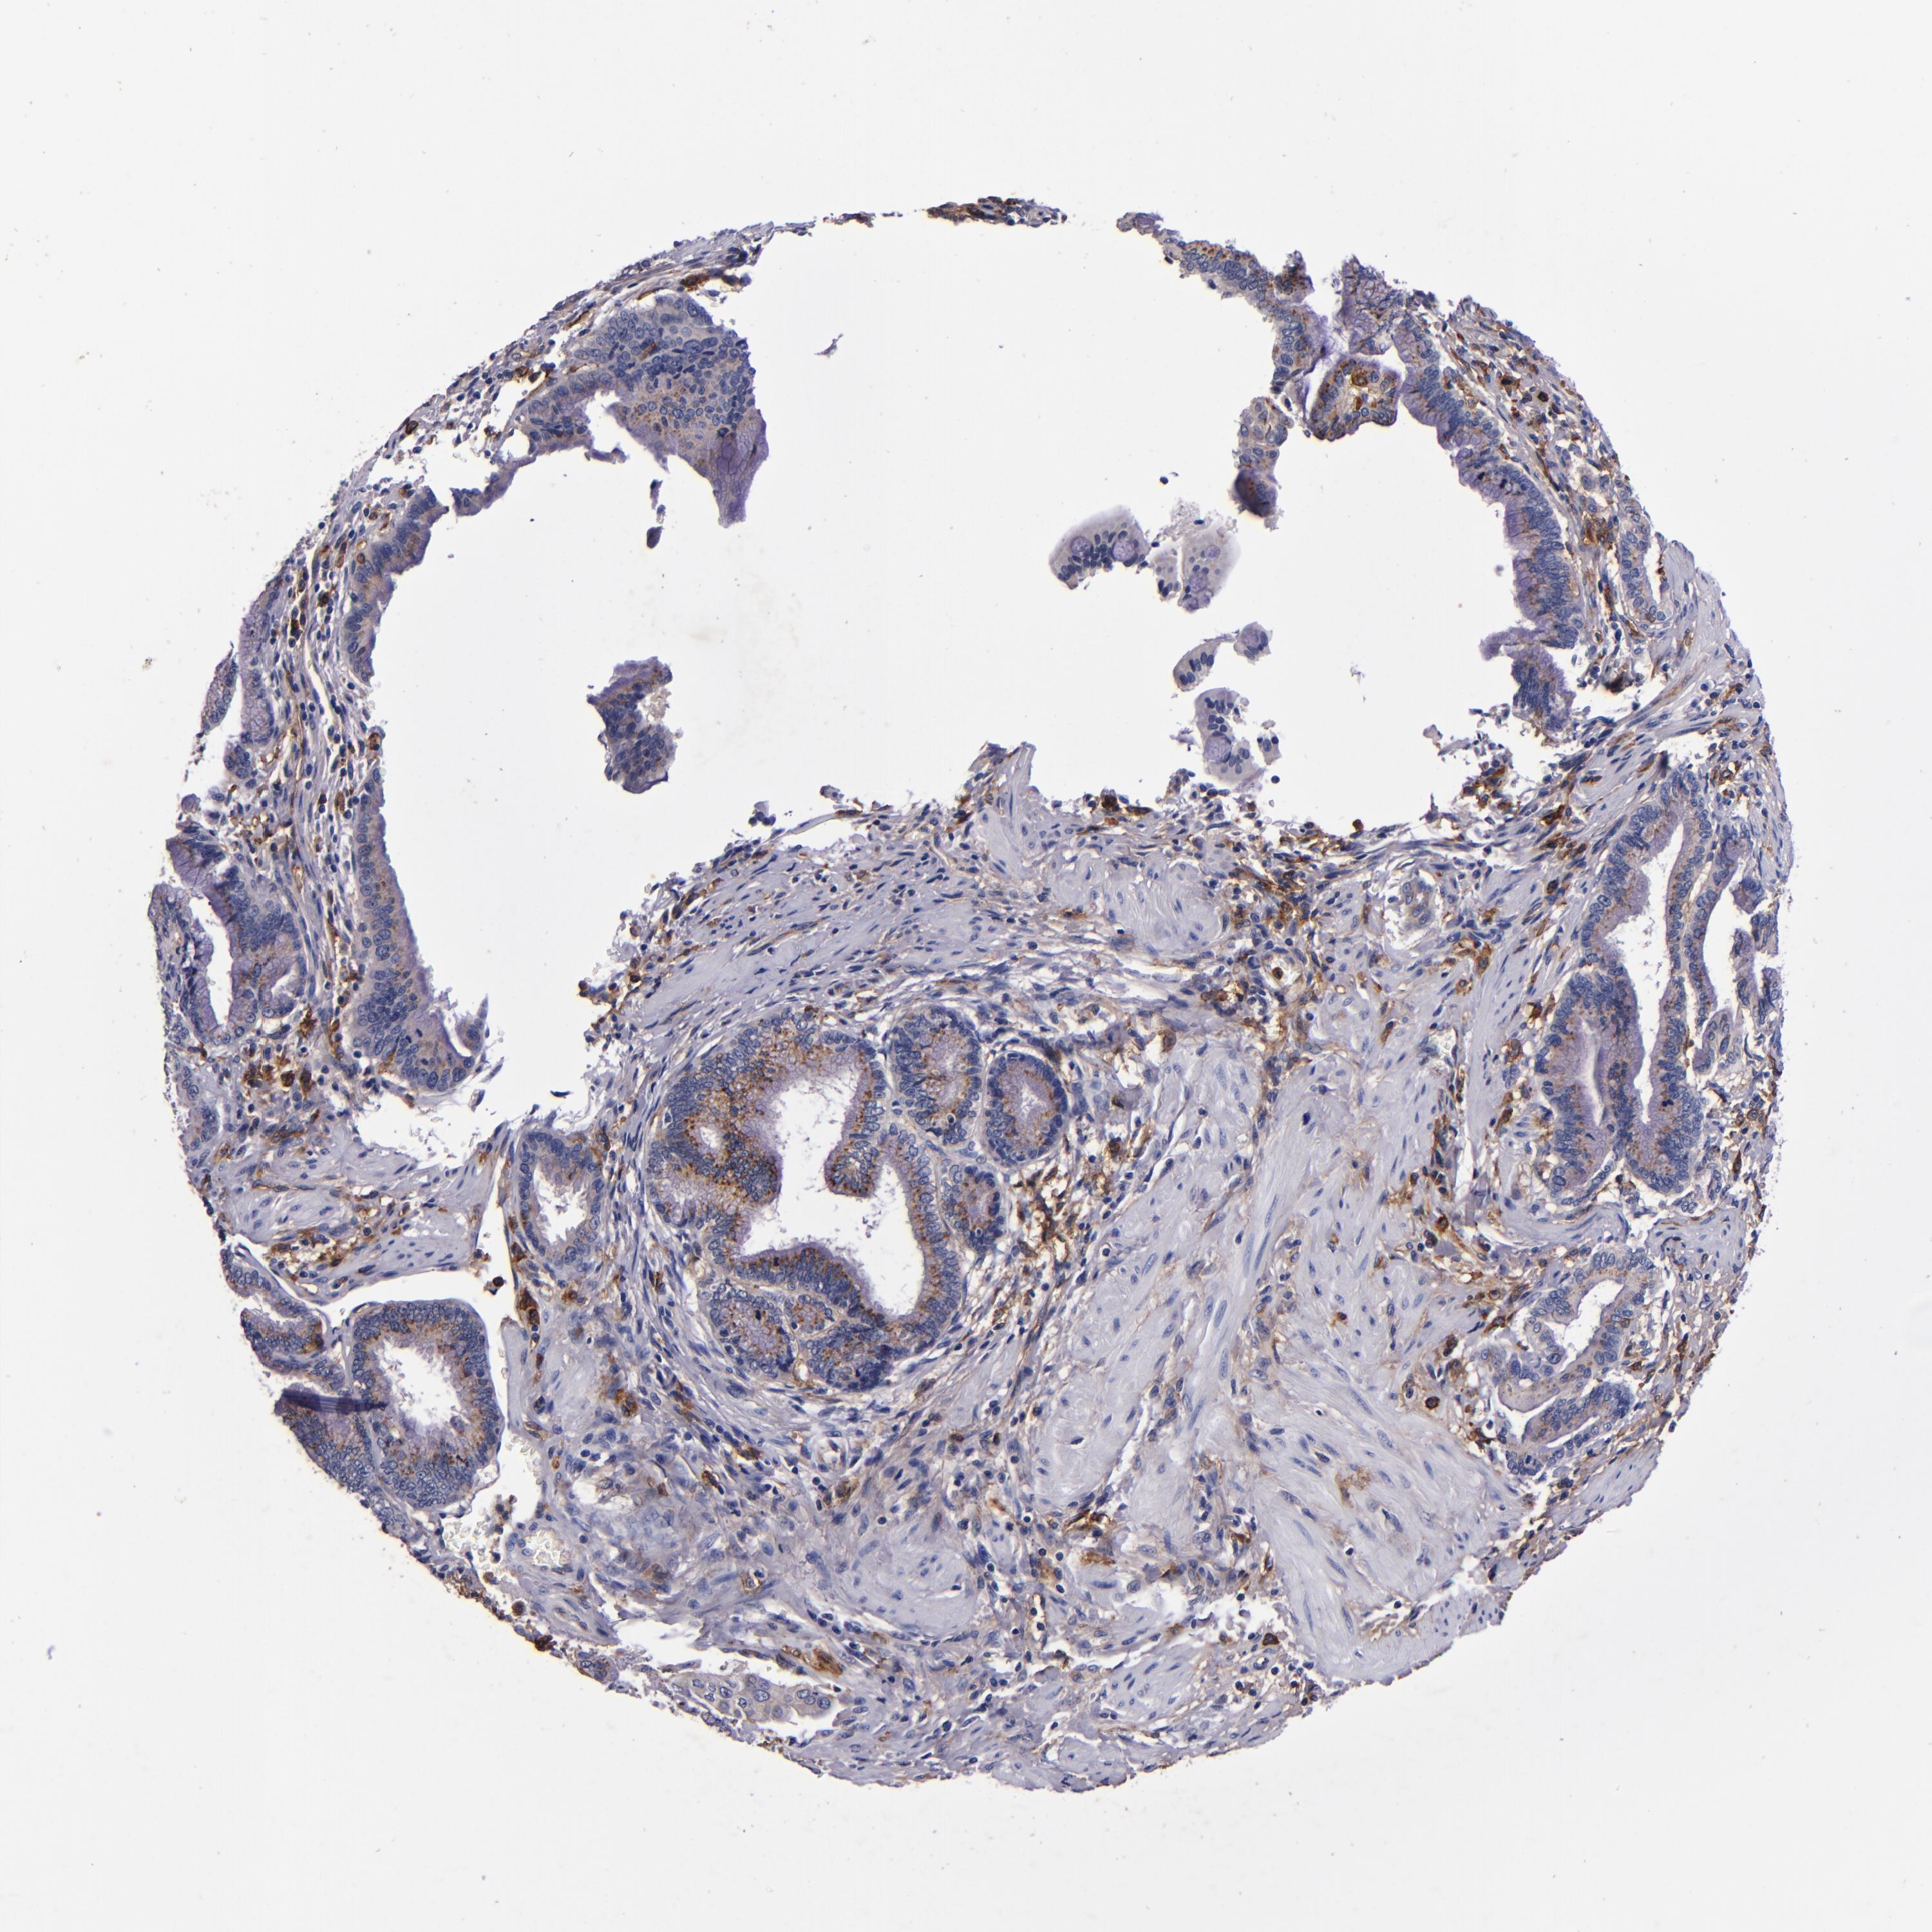

PANCREATIC CANCER - Protein expressioni

A mouse-over function shows sample information and annotation data. Click on an image to view it in a full screen mode. Samples can be filtered based on level of antibody staining by selecting one or several of the following categories: high, medium, low and not detected. The assay and annotation is described here.

Note that samples used for immunohistochemistry by the Human Protein Atlas do not correspond to samples in the TCGA dataset.

Antibody stainingi

Antibody staining in the annotated cell types in the current human tissue is reported as not detected, low, medium, or high, based on conventional immunohistochemistry profiling in selected tissues. This score is based on the combination of the staining intensity and fraction of stained cells.

Each image is clickable and will lead to virtual microscopy that enables deeper exploration of all samples and also displays staining intensity scores, fraction scores and subcellular localization as well as patient and tissue information for each sample.

Antibody HPA054437

Antibody HPA058511

Antibody CAB002776

Antibody CAB015122

Adenocarcinoma, NOS

Adenocarcinoma, metastatic, NOS